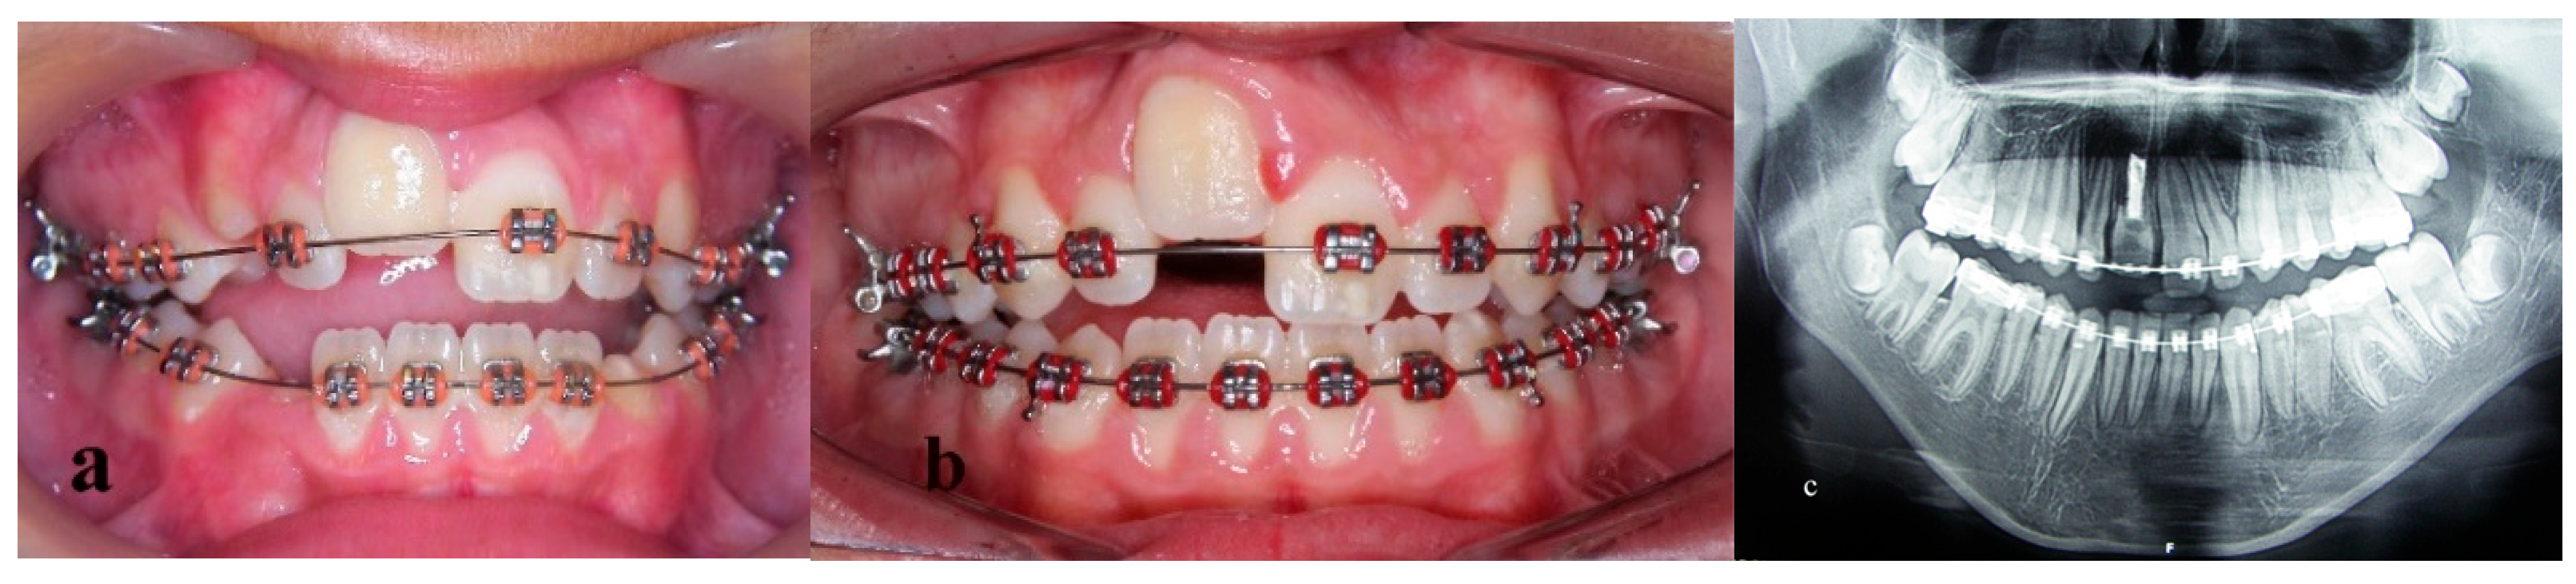

Treatment of an Avulsed and Ankylosed Incisor through Single Tooth Alveolar Osteotomy and Conventional Orthodontic Mechanisms

2. Materials and Methods

3. Results